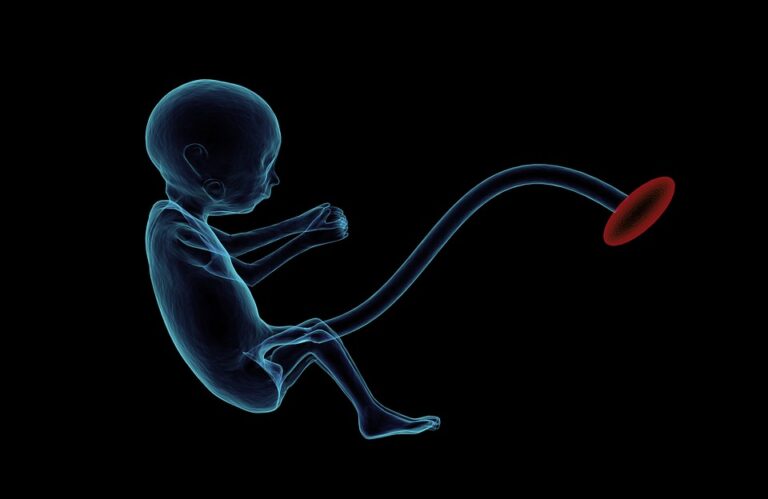

Obezita může způsobit neplodnost i potrat

Těhotné ženy, které jsou zároveň obézní, mají až o třetinu vyšší riziko, že nedonosí dítě. Potvrzují to nejnovější výsledky španělské studie Ženská obezita zvyšuje riziko potratu geneticky zdravého embrya. Vysoká tělesná hmotnost mužů i žen také často brání už samotnému početí. V tuzemsku se s obezitou podle Českého statistického úřadu potýká každý pátý Čech a Češka. […]

Nové naděje pro početí

Téměř v každé ženě s postupem času vzklíčí touha stát se matkou, k mnohým z nich však bývá příroda nemilosrdná a jejich přání ne a ne vyslyšet. Naštěstí žijeme v době, kdy si moderní medicína dokáže poradit. Neplodnost, ať už ženská, nebo mužská, se často řadí mezi současné civilizační choroby. Je mnoho faktorů, které způsobují, […]